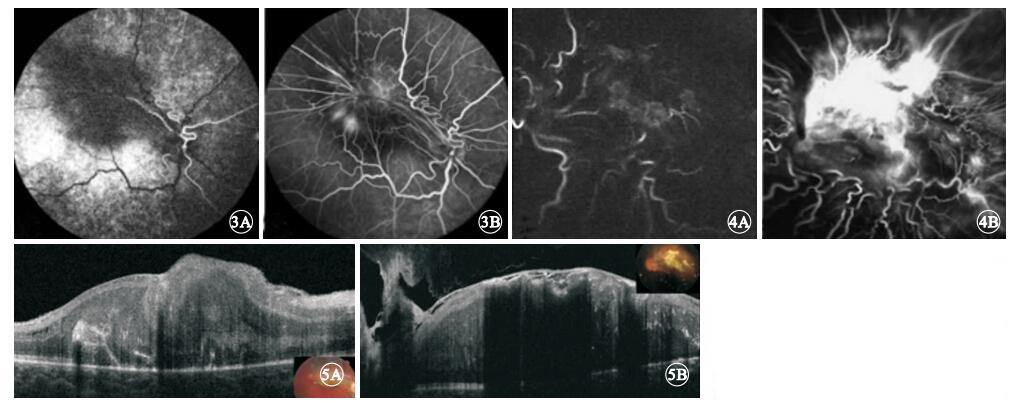

所有患眼的CHRRPE病灶均位于后極部,呈不同程度的黃白色隆起,其周圍深層視網膜均因色素沉著而呈灰黑色,瘤體表面有不同程度的灰白色纖維膜增生,視網膜因纖維膜牽引而呈現皺褶,視網膜血管呈螺旋樣紆曲向病變中央走行(圖 1);均無出血及滲出。8只眼中,累及黃斑和視盤3只眼,占37.5%;僅累及黃斑5只眼,占62.5%。

圖1

CHRRPE患眼彩色眼底像。1A. 9歲患兒右眼彩色眼底像;1B. 21歲患者左眼彩色眼底像。黃斑區有黃白色隆起病灶,其附近深層視網膜色素沉著,病灶表面有視網膜前纖維膜與視盤相連,視網膜血管紆曲

圖1

CHRRPE患眼彩色眼底像。1A. 9歲患兒右眼彩色眼底像;1B. 21歲患者左眼彩色眼底像。黃斑區有黃白色隆起病灶,其附近深層視網膜色素沉著,病灶表面有視網膜前纖維膜與視盤相連,視網膜血管紆曲

FFA檢查發現,造影早期即可見所有患眼病變部位及其周圍脈絡膜背景熒光均減弱,且其持續存在于整個造影過程中;靜脈期可見因纖維膜收縮、牽引而呈螺旋樣紆曲的視網膜血管走行;病灶處視網膜毛細血管擴張、熒光素滲漏,病變部位熒光亮度逐漸增強(圖 3,4)。均未發現視網膜出血、滲出、毛細血管無灌注區、視網膜新生血管及脈絡膜新生血管等異常。

所有患眼的CHRRPE病灶均位于后極部,呈不同程度的黃白色隆起,其周圍深層視網膜均因色素沉著而呈灰黑色,瘤體表面有不同程度的灰白色纖維膜增生,視網膜因纖維膜牽引而呈現皺褶,視網膜血管呈螺旋樣紆曲向病變中央走行(圖 1);均無出血及滲出。8只眼中,累及黃斑和視盤3只眼,占37.5%;僅累及黃斑5只眼,占62.5%。

圖1

CHRRPE患眼彩色眼底像。1A. 9歲患兒右眼彩色眼底像;1B. 21歲患者左眼彩色眼底像。黃斑區有黃白色隆起病灶,其附近深層視網膜色素沉著,病灶表面有視網膜前纖維膜與視盤相連,視網膜血管紆曲

圖1

CHRRPE患眼彩色眼底像。1A. 9歲患兒右眼彩色眼底像;1B. 21歲患者左眼彩色眼底像。黃斑區有黃白色隆起病灶,其附近深層視網膜色素沉著,病灶表面有視網膜前纖維膜與視盤相連,視網膜血管紆曲

FFA檢查發現,造影早期即可見所有患眼病變部位及其周圍脈絡膜背景熒光均減弱,且其持續存在于整個造影過程中;靜脈期可見因纖維膜收縮、牽引而呈螺旋樣紆曲的視網膜血管走行;病灶處視網膜毛細血管擴張、熒光素滲漏,病變部位熒光亮度逐漸增強(圖 3,4)。均未發現視網膜出血、滲出、毛細血管無灌注區、視網膜新生血管及脈絡膜新生血管等異常。